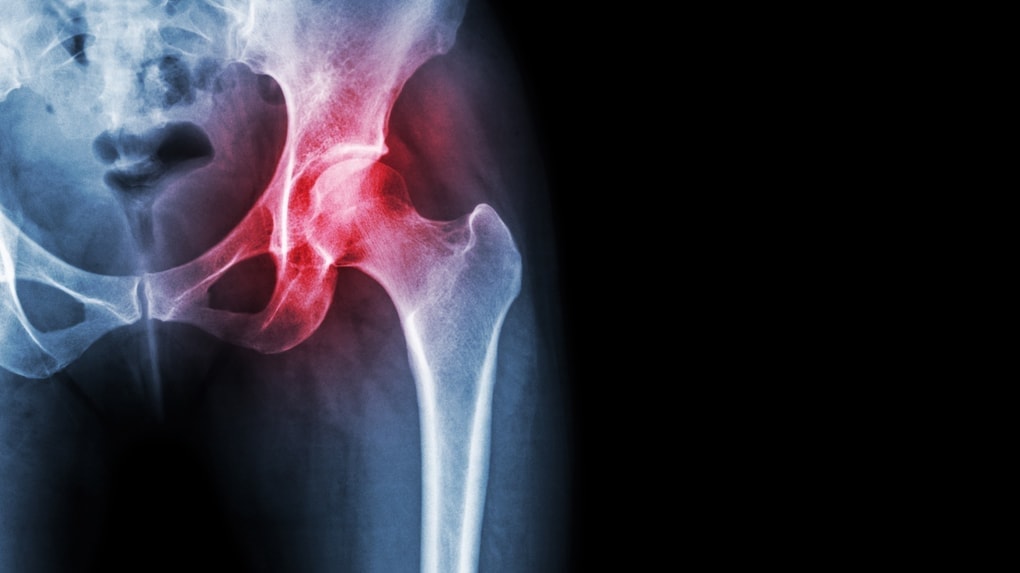

腰痛の放置は回復が遅くなるのに加えて、慢性化や腰椎椎間板ヘルニアに発展したりします。

腰椎椎間板ヘルニアは神経を圧迫する症状で、痛みやしびれに感覚の消失なども起こります。

脊柱管狭窄症は腰椎椎間板ヘルニアと似ていますが、背骨が無理に曲がることで起こります。

と考えた時にとても重要になってくるのは「骨盤」です。

この負担を支えるために腰椎と骨盤はとてもとても面積の広い安定した関節の構造になっています。

しかし、安定しているとはいえ背骨を乗せている骨盤が、もし傾いていたとしたらどうでしょう?